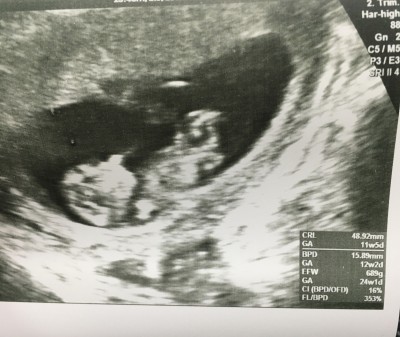

Keseye göre nub teorisi ramzi teorisi bilenler yorumlayabilir mi

Doktor cıkıntı var gibi ama daha erken dedi canım

Crl nasıl yüksek canım googleden baktım yüksek değil  sanki

Cnm burda gecen bi yorumlarda okumustum crl 40 50 lerde ise kiz 7.8 flansa erkek oluyormus diye ve 12.haftada crl miz 5.37 ymis simdi baktim ultrason fotolarina oglum oldu benim 6 aylik olacak:))

Kız doğdu içime bilmiyorum. Bilgim de yok cinsiyet yorumlama hakkında. Ama bana kız gibi geldi. Sağlıkla doğur<3:)

Kıza benzetiim :)